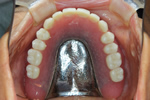

治療後

磁石を埋め込んだ入れ歯が入りました。磁石により維持や安定が得られるため、上顎全体を覆う必要がなく、違和感の少ない義歯を作ることができました。また、下顎の奥歯の治療も同時に行い、噛み合わせの歪みも無くなり、しっかり噛めるようになりました。